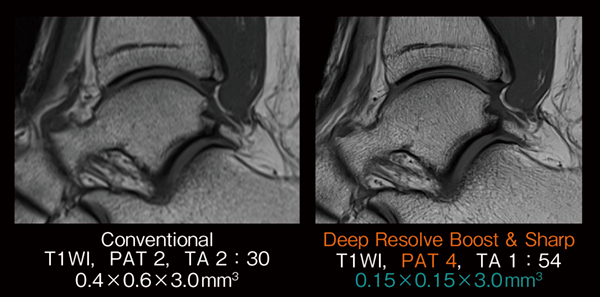

さらに,Deep Resolveは多断面同時励起法であるSMSとも併用が可能であり,従来は困難であった超高倍速による撮像に応用されている2)。図3の例では,2D撮像において8倍速という高倍速撮像が実用化されており,1〜1.5mmのthin slice撮像を1分台の短時間で完結している。また,1mmスライス厚で撮像された膝関節のT1強調画像においては,2D撮像でありながらMPRにおいても画質を担保できている。このように,thin sliceの2D撮像を応用することで,3D撮像の欠点であるコントラストの低下やブラーリングによるボケをカバーしながら,パーシャルボリューム効果などの影響を低減できるため,診断能向上が期待できる。

図3 Deep Resolve と SMSの併用

多断面同時励起を用いて,撮像枚数の多くなるthin slice撮像でさらなる高速化が可能となる。